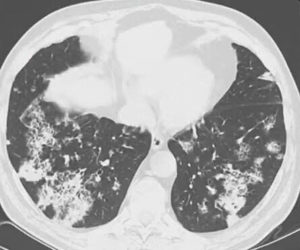

Что показывает компьютерная томография легких

На снимках рентгенолог видит картину вирусного поражения, которая в общих чертах мало отличается от картинки при гриппе. То есть поставить диагноз именно ковидной пневмонии по КТ нельзя.

Характерными признаками действия вируса будут изменения легочных полей в виде очагов (от одиночного до диффузных). Вирусная пневмония выглядит на томографии легких как совокупность типичных изменений.

- «Матовое стекло» — очаг просветления легочного поля из-за снижения воздушности в сочетании воспаления и утолщения межальвеолярных перегородок, заполнения альвеол жидкостью.

- Очаги округлые, могут сливаться между собой и распространяться на большую часть легочного поля. Чаще располагаются на периферии ближе к плевре. Чаще в нижних сегментах.

- «Булыжная мостовая» — утолщение пространства между легочными дольками, за счет чего они выглядят, как разрозненные части дороги.

- Консолидация — уплотнение легочной ткани за счет заполнения альвеол жидкостью.

- Симптом обратного ореола — кольцо консолидации вокруг участка “матового стекла”

- «Воздушная бронхограмма» — просвет бронха, пересекающего участок уплотнения легкого.

- Отмечается чаще двустороннее поражение.

- В отличие от бактериальной пневмонии реже наблюдается усиление легочного рисунка.

Приоритетным экспертным методом диагностики легких и бронхов считается компьютерная томография. Она способна точно воспроизводить детали изображения с охватом широкого спектра плотностей легочной ткани и выявлять начальные признаки морфологической перестройки при опухолевом и некротическом поражении. На первом этапе пациентам с заболеваниями легких обычно назначают выполнить рентгенографию в стандартных проекциях для исключения очаговых и инфильтративных изменений в легких. Если данные рентгеновских снимков носят тревожный характер, для уточнения диагноза, дифференциальной диагностики болезни легких и бронхов вторым шагом врач назначит сделать мультиспиральную компьютерную томографию органов грудной клетки. Она позволяет идентифицировать все мелкие повреждения в легочной ткани, которые имеют особое клиническое значение при выявлении опухолей, пневмонии, астмы, туберкулёза, хронической обструктивной болезни легких. Если данные КТ легких предполагают наличие злокачественного поражения, в качестве дополнительного метода могут назначить пройти МРТ легких с контрастом, чтобы оценить степень инвазии опухоли в ткани средостения и лимфатические узлы.

Компьютерный томограф получает изображения за счет способности рентгеновских лучей проходить сквозь ткани различной плотности с разной скоростью. В легких содержится много воздуха, потому рентгеновские лучи в них не задерживаются, что дает хорошую тканевую контрастность, если в легких и бронха есть новообразования. Поскольку КТ аппарат делать множественные снимки с большой скоростью, он менее чувствителен к артефактам движения. Все это делает КТ более точными информативным методом диагностики легочных заболеваний по сравнению с магнитно-резонансной томографией.